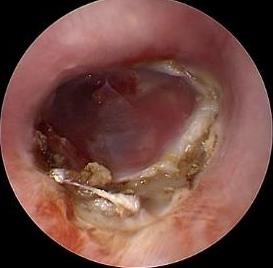

• 耳内镜下耳屏软骨-软骨膜鼓膜修补术后的短期疗效观察

摘要:目的 探讨耳内镜下耳屏软骨-软骨膜鼓膜修补术后的短期疗效。方法 回顾性分析2019年9月-2022年8月该院收治的78例鼓膜穿孔患者的临床资料,患者均采用耳内镜下鼓膜修补术。术后随访3个月,观察鼓膜形态和穿孔愈合情况,记录内镜图像、干耳时间、术前术后听力及耳鸣情况,以及外耳道狭窄等并发症的发生率。结果 术后3个月,鼓膜穿孔愈合率为97.44%(76/78),愈合良好,平均气导听阈较术前明显改善,气骨导间距较术前明显缩小,耳鸣较术前明显改善,差异均有统计学意义(P<0.05)。干耳时间为(4.21±1.12)周。术后出现肉芽5例,再穿孔2例,真菌感染2例,术腔感染、耳屏感染、外耳道狭窄和切口瘢痕各1例,所有患者术后均未发生面神经麻痹和感音神经性聋等严重并发症。结论 耳内镜下耳屏软骨-软骨膜鼓膜修补术是一种安全、有效的手术方法。根据术后愈合规律、内镜下鼓膜和外耳道形态特征,可为鼓膜修补术后正常中耳转归和并发症的诊疗,提供临床参考。